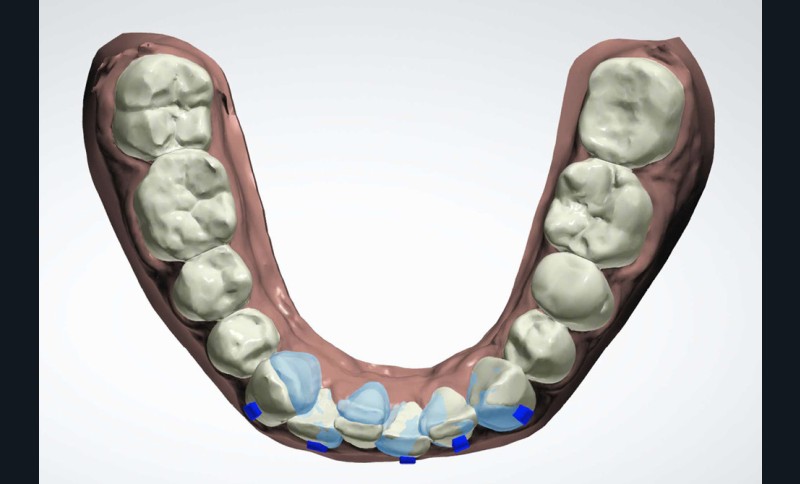

(fig. 4 à 10)

Le plan de traitement établi conjointement avec son chirurgien-dentiste traitant consiste à réaliser un alignement dentaire mandibulaire et à réaliser des extractions de 16 et 15 pour un remplacement par prothèse implanto-portée.

La durée orthodontique prévue est de neuf mois, avec comme contrainte principale l’absence de possibilités de modification des formes d’arcades.

Le gain de place se fera par des réductions interproximales sur la zone incisivo-canine mandibulaire.

Il est décidé de ne pas redresser la 43 complètement afin de ne pas entraîner d’interférences occlusales.

Un accompagnement par des meulages occlusaux est réalisé.